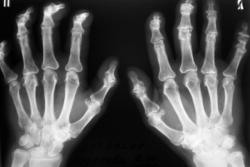

Катенёв Валенти... Дата публикации 25.06.2009, 00:50 Пациент направлен терапевтом в рентгеновский кабинет "на рентгенографию кистей", с диагнозом "Ревматоидный артрит". Ваше мнение коллеги? Чт, 25/06/2009 - 07:54 #1 Андрей Юрьевич Не на сайте Был на сайте: 2 недели 2 дня назад Зарегистрирован: 16.11.2008 - 22:16 Публикации: 18098 Сложно сказать, нет решающего рентген-признака: периартикуллярного остеопороза. В данном случае надежда на лабораторные данные, это ведь и подагрой (см. ниже http://www.radiomed.ru/cases/podaghrichieskii-artrit ) может быть. Андрей Юрьевич Чт, 25/06/2009 - 18:13 #2 OPEXOB Не на сайте Был на сайте: 9 лет 11 месяцев назад Зарегистрирован: 26.07.2008 - 10:02 Публикации: 280 Ревматоидный полиартрит, 4 рентгенологическая стадия. Судя по положению кистей, особенно дистальных фаланг имеет место контрактура данных сочленений. Анализы? СОЭ? Клиника? Чт, 25/06/2009 - 18:45 #3 Андрей Юрьевич Не на сайте Был на сайте: 2 недели 2 дня назад Зарегистрирован: 16.11.2008 - 22:16 Публикации: 18098 ///Анализы? СОЭ? Клиника?/// Выходит Петр. Он ужасен, Движенья быстры, Он прекрасен, Он весь как божия гроза (с) Андрей Юрьевич Чт, 25/06/2009 - 19:20 #4 OPEXOB Не на сайте Был на сайте: 9 лет 11 месяцев назад Зарегистрирован: 26.07.2008 - 10:02 Публикации: 280 Ха,ха, очень смешно!

Сложно сказать, нет решающего рентген-признака: периартикуллярного остеопороза. В данном случае надежда на лабораторные данные, это ведь и подагрой (см. ниже http://www.radiomed.ru/cases/podaghrichieskii-artrit ) может быть.

Ревматоидный полиартрит, 4 рентгенологическая стадия. Судя по положению кистей, особенно дистальных фаланг имеет место контрактура данных сочленений.